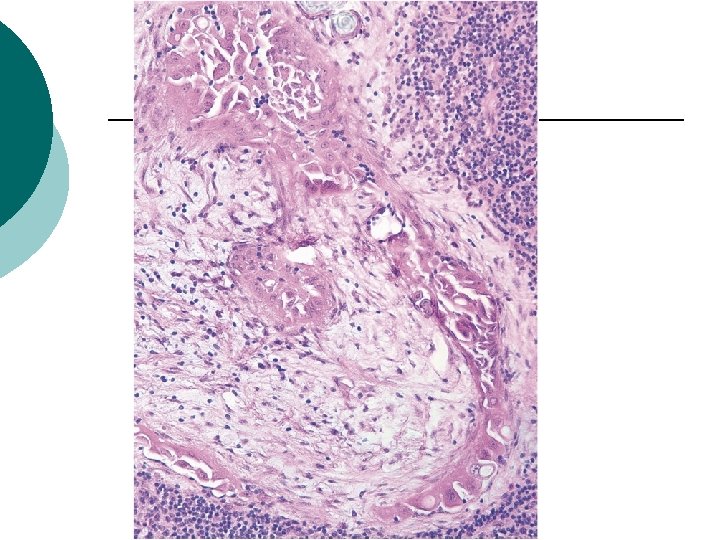

Nodular aggregate

Extent and Location of Lymph Node Involvement Nodular aggregate:was defined as a collection of epithelium without intervening lymphoid tissue measuring greater than 1 mm in linear dimension Ps: diffuse LNI was characterized by epithelial cells of any morphologic pattern scattered throughout the lymph node (ie, not focal), but with intervening lymphoid tissue. ¡ Nodular aggregates were strongly associated with desmoplastic fibrous stromal reaction (P=0. 001) and micropapillary architecture (P=0. 02). ¡ Disease-free survival versus LNI without this pattern : 25% versus 87% (P=0. 02) significience ¡